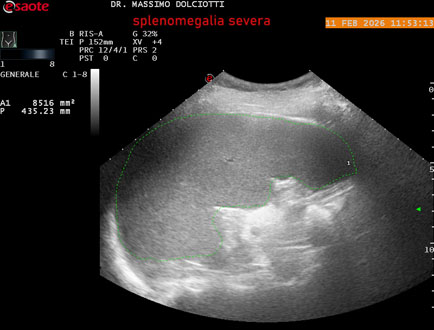

Data inserimento: 18/02/2026

Ecografia del: 11/02/2026

Strumento: Esaote MyLab Eight

Sonda: Conevx Multifrequenza 1-8 MHz

Età Paziente: F 68 anni

Motivazione dell'esame: follow up di splenomegalia.

Commento all'esame: le immagini ed il video documentano la milza con ecostruttura normale e morfovolumetria superiore alla norma, con diametro bipolare di 159 mm (v.n. 70-120 mm) ed area di sezione di 101 centimetri quadri (v.n. < 47 centimetri quadri).

Conclusioni: splenomegalia di severa entità (severe splenomegaly).